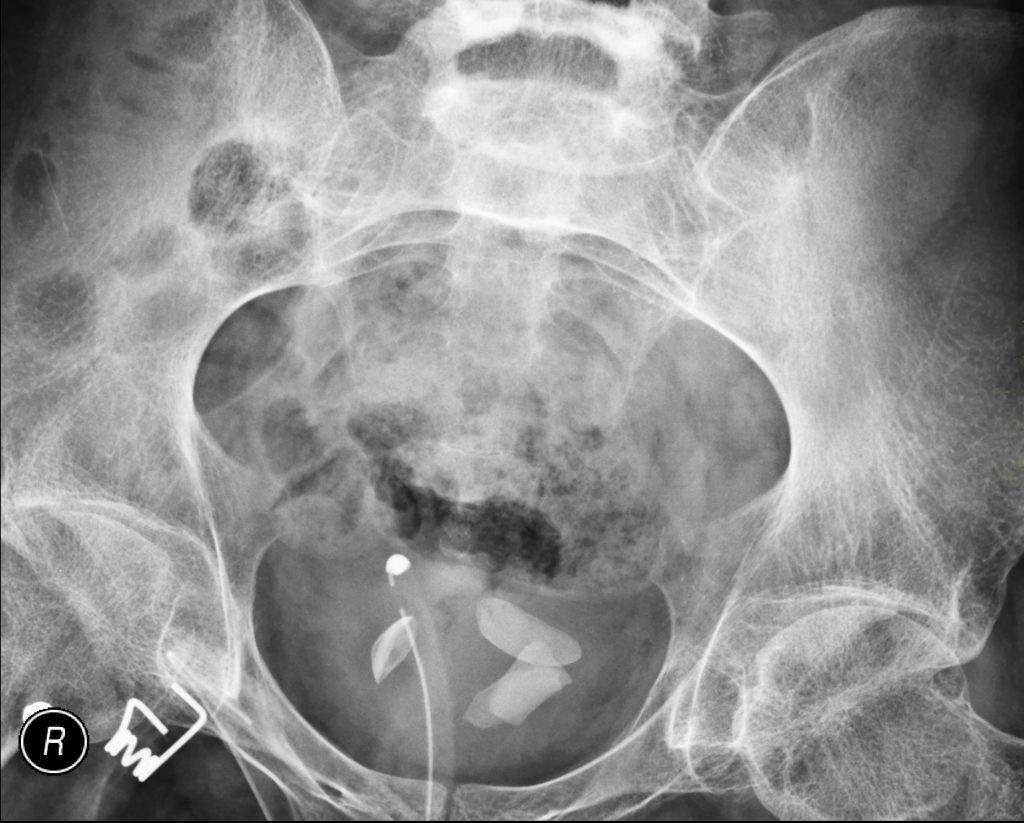

Doenças do trato urinário

As doenças do trato urinário incluem infecções urinárias, cálculos renais (pedras nos rins), incontinência urinária, obstrução uretral e doenças da bexiga, uretra e ureteres. Discutiremos os sintomas, diagnóstico e tratamento dessas condições, fornecendo uma visão geral abrangente.